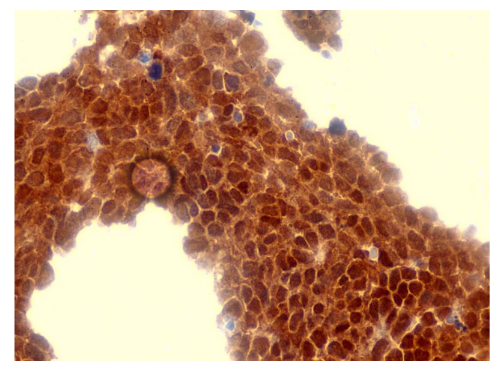

Figure 4 depicts an immunohistochemically stained section of cervical tissue showing diffuse nuclear positivity. Brown chromogen deposits within the nuclei indicate expression of p53 biomarker, while the blue counterstain (hematoxylin) highlights the nuclei of negative or unstained cells and background tissue architecture. The staining appears strong and widespread across the epithelial cell layers, suggesting high biomarker expression consistent with advanced dysplasia or high-grade cervical intraepithelial neoplasia.